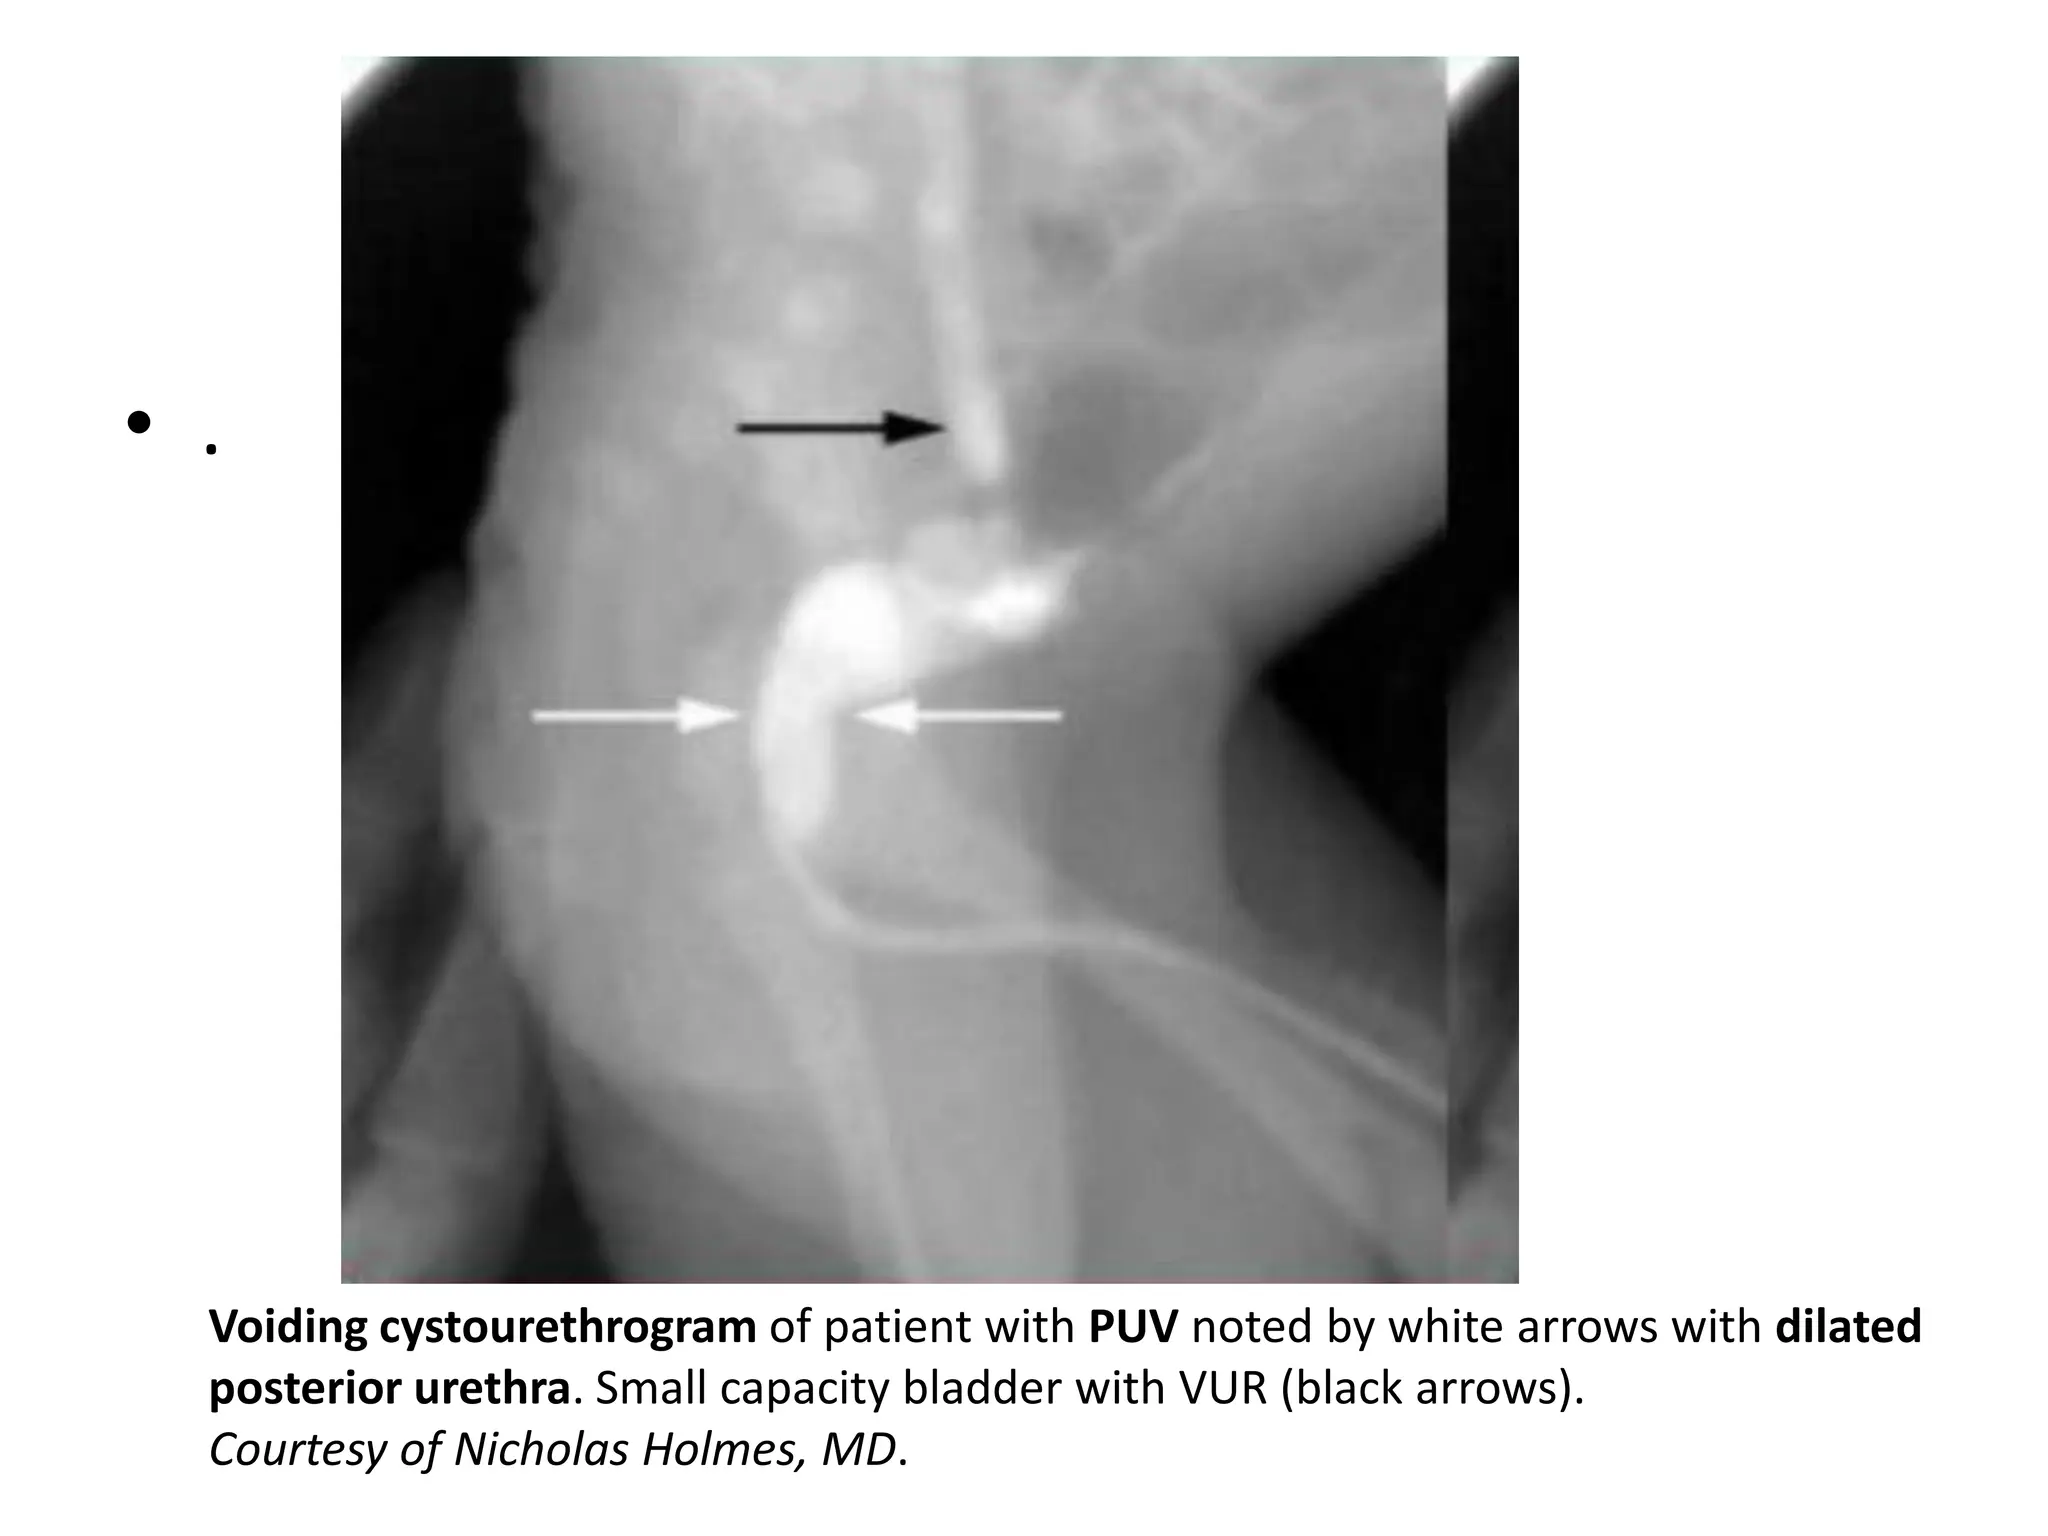

Diagnosis

• Diagnosis: Micturating cystourethrogram

(MCUG)

– hallmark is dilated, elongated posterior urethra

with a thin linear defect during the voiding phase;

• Confirmed diagnosis: cystoscopy.

Voiding cystourethrogram of patient with PUV noted by white arrows with dilated

posterior urethra. Small capacity bladder with VUR (black arrows).

Courtesy of Nicholas Holmes, MD.